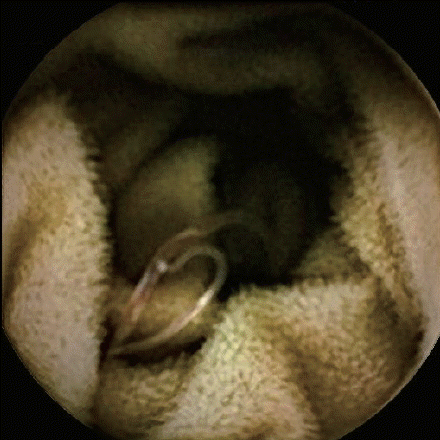

The patient underwent a CTA of the abdomen, which showed multiple deep vein thrombosis, but without definite evidence of gastrointestinal bleeding, retroperitoneal hematoma, or acute mesenteric ischemia (AMI). Gastroscopy showed hookworms in the duodenum, and the intestine is thought to be the source of bleeding (

Fig. 2). A capsule endoscopy demonstrated fresh blood in the jejunum and multiple worm-like objects in the jejunum and ileum, all with a similar curvature and large “heads” (

Fig. 2Gastroscopy showing red worms swimming in the duodenum.